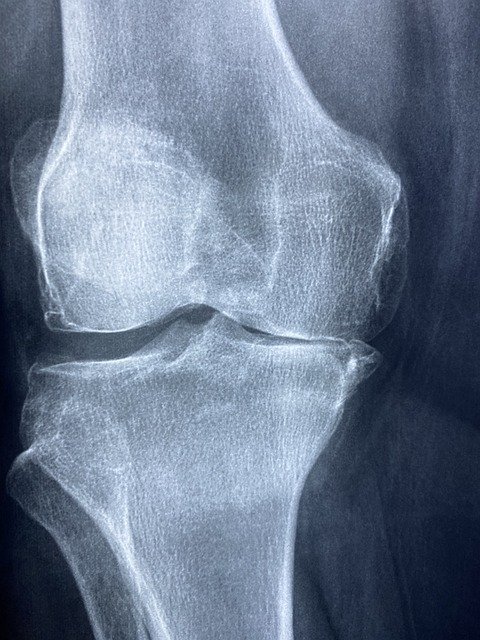

Le chirurgien orthopédiste joue un rôle essentiel dans le maintien de votre santé articulaire. Spécialiste des os, des muscles et des ligaments, il tr...